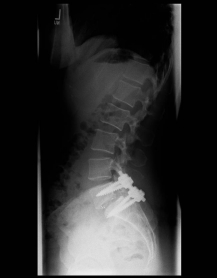

Spondylolisthese

Spondylolisthesis refers to a slipped vertebra, i.e. a displacement of the upper vertebra with respect to the lower one. This can occur degeneratively due to joint wear or due to a disruption of the vertebral arch, which is usually a consequence of an unnoticed and unhealed fracture. A slipped vertebra often becomes symptomatic through an instability-related pain on exertion (getting up from a chair is only possible with the help of the arms). However, it is not uncommon for the vertebral displacement to lead to secondary spinal canal stenosis, which then becomes noticeable as pain extending into the legs.

X-ray image of a slipped vertebra in the lower lumbar spine before and after surgery